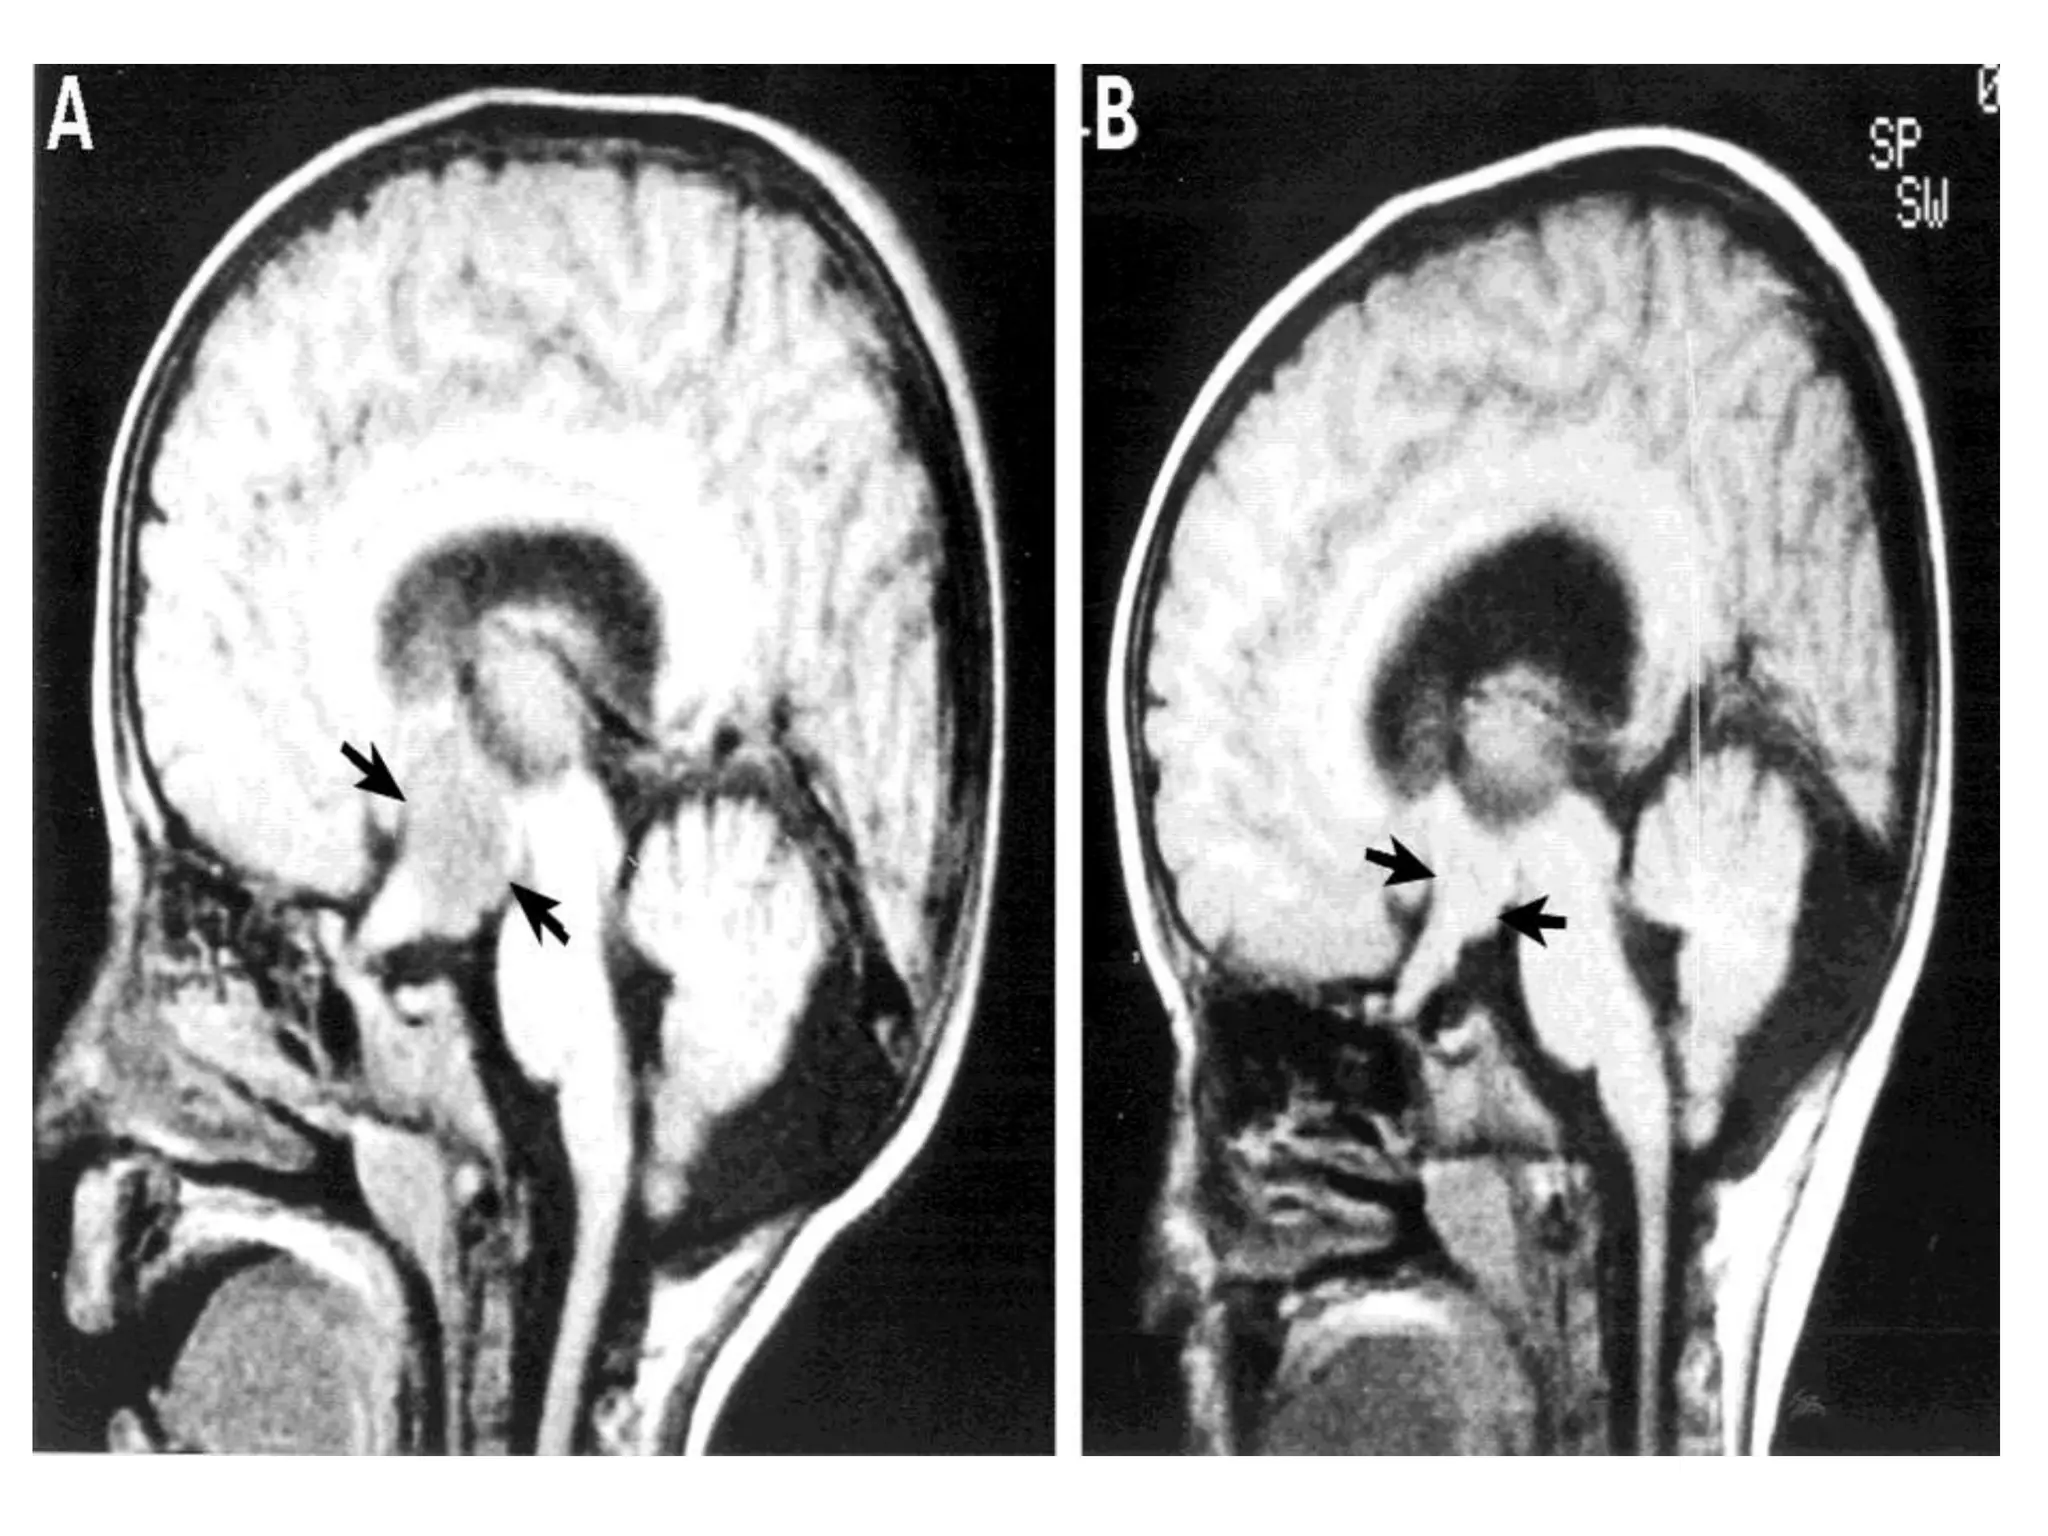

Upward herniation

Upward herniation Increased pressurein the posterior fossa can cause the cerebellum to move up through the tentorial opening in upward, or cerebellar herniation. The midbrain is pushed through the tentorial notch.